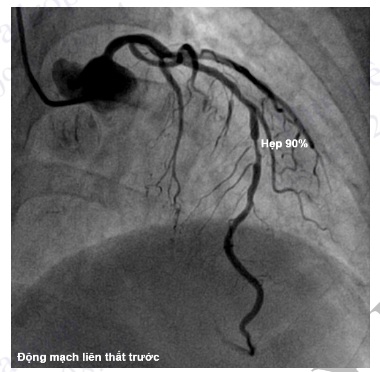

Mức độ hẹp thường biểu thị bằng tỷ lệ phần trăm (%) độ hẹp so với đoạn mạch vành bình thường ngay sát chỗ hẹp. Gọi là hẹp nhiều (hẹp đáng kể) khi mức hẹp >70%.

Hình 4.95. Chụp ĐMV trái ở tư thế chếch đầu 30° cho thấy hẹp khít 90% đoạn giữa động mạch liên thất